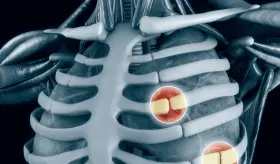

El dolor provocado por la costocondritis puede simular un ataque al corazón, problemas articulares o enfermedades pulmonares.